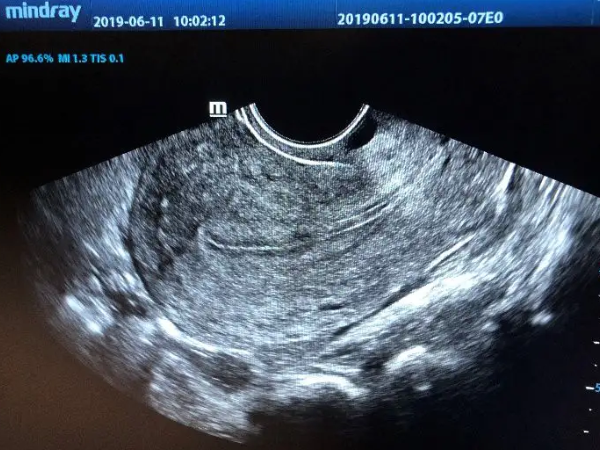

子宫内膜厚4.4mm如果处于增殖期,是属于一种正常的现象。内膜在月经周期的第五天是最薄的,在月经前潮前是最厚的,增殖期是月经周期第5日到第14日,子宫内膜厚度从0.5毫米到5毫米,这时子宫内膜增殖的早期,内膜是最薄的。并且内膜在4.4mm也就是正常的,但如果正除去月经期或分泌期,这个厚度显然是偏薄的。

随着月经周期的结束,由于激素水平的作用,子宫内膜开始逐渐的增厚。在月经前,也就是分泌期,子宫内膜可能会达到10-18mm,所以内膜的厚薄要随着月经周期变化而变化。如果是在月经前内膜4.4mm,那就说明子宫内膜太薄。子宫内膜过薄可能会造成不孕症,或者是月经量过少,临床就需要进行治疗。

是不可以移植的,做试管婴儿要移植胚胎的时候,子宫内膜的厚度需要达到7mm才行,通常内膜7-14mm属于是可移植的范围,8mm是最合适移植胚胎的厚度,如果内膜偏薄或偏厚都是不利于胚胎着床的,会影响到怀孕,基本是自然怀孕的,如果内膜4.4mm也是会影响到受精卵着床的。